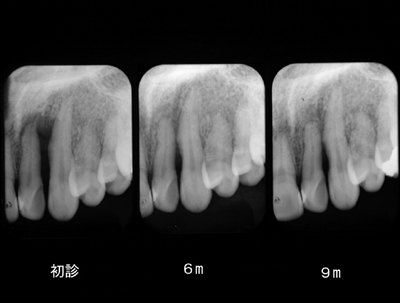

咬合性外傷

左上犬歯近心の骨欠損です。

EPT+.プラークコントロールが非常に良い方で赤染めではほとんどどこも染まりません。

ブラキシズムによる外傷と診断し、スケーリング、ルートプレーニングは一切せずナイトガードと自己暗示療法による外傷のコントロールを試みました。

初診と3ヶ月後の比較です。骨が少しずつ戻ってきました。